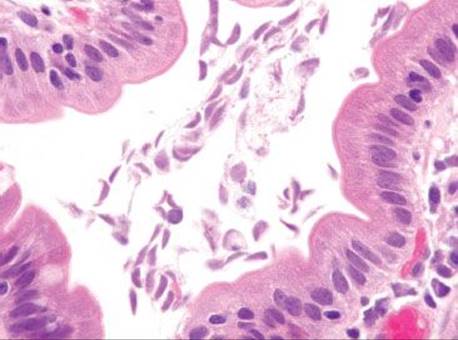

Figure 3.315 Sneaky adenocarcinoma involving the duodenal mucosa. Under oil immersion, note the nuclear irregularities, abundant pink cytoplasm, and cytoplasmic mucin droplet (arrowhead) characteristic of pancreatobiliary adenocarcinoma. Unfortunately, sometimes 38 levels are required for the ultimate diagnosis and sometimes only a few malignant cells are present! When the clinical scenario and the histology are not aligned, deeper sections (and deeper sections and deeper sections and deeper sections) are often required.